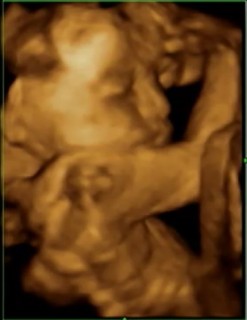

26w1dのエコーです(°▽°) 性別は 女の子かな?っと言われてますが、まだ確定ではないです(..) 目が開いてて、おもわず「怖っ!」って言ってしまいました~!笑 次から二週間に一度の検診になったので楽しみです。